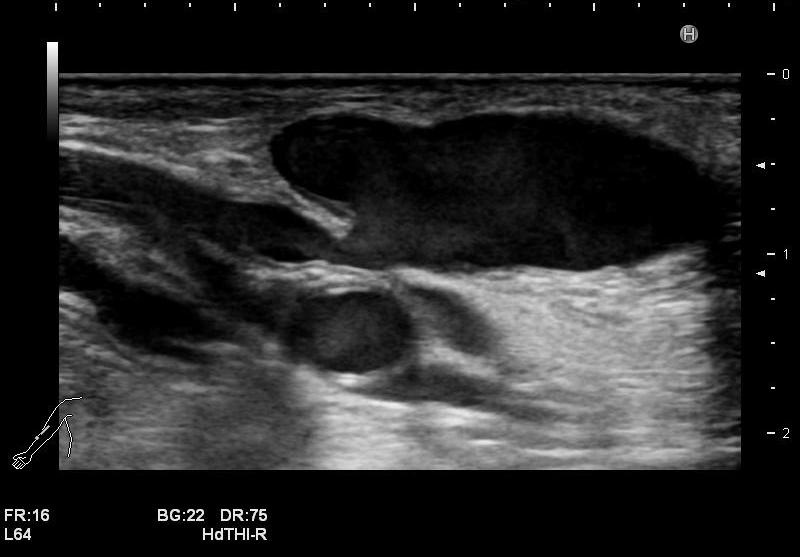

石灰化画像

吻合部画像

・吻合部の観察

吻合形態や、石灰化の有無、狭窄等を観察しています。